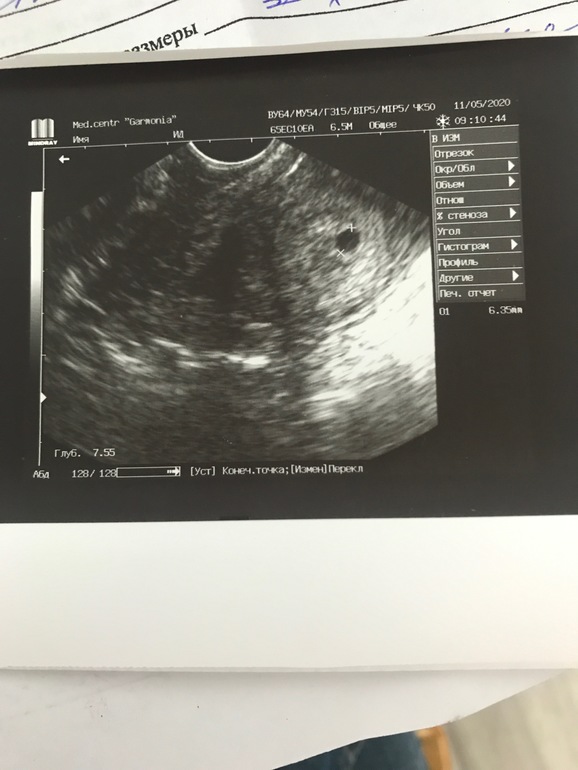

Девчонки, вот и сходила я на долгожданное узи, немного полегче стало, но не до конца. В полости матки плодное яйцо 10*14 мм. Срок поставили 5 недель, эмбриона ещё нет, там амниотический мешок из которого формируется эмбрион. По узи все соответствует сроку, все развивается. Контроль узи через 10 дней, должно быть сердечко уже вот на 20 записалась❤️

Вот мое УЗИ в 6,5 недель, было только плодное яйцо и желточный мешочек. Через 1,5 недели снова пришла, уже был эмбрион 10 мм и сердцебиение 💓. Не переживайте, хотя сама такая же😩